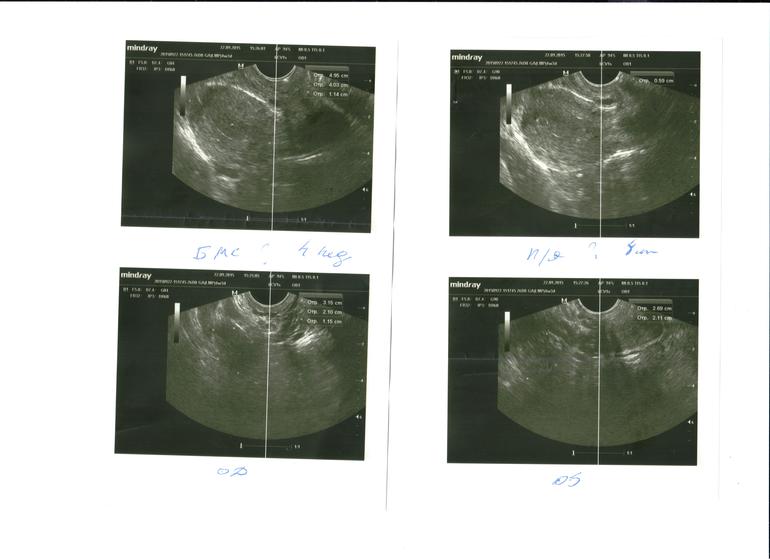

Моё УЗИ в 5 недель

Вопросы про УЗИ, обследования и анализы: что, где, как, когда?Шла я на УЗИ с определенной целью - исключить внематочную беременность. Честно говоря думала,что нет вообще никакой беременности,но призрак на тесте меня напугал и я побежала. Врач увидела плодное яйцо в матке. Девочки помогите расшифровать, вы тоже видите плодное яйцо?